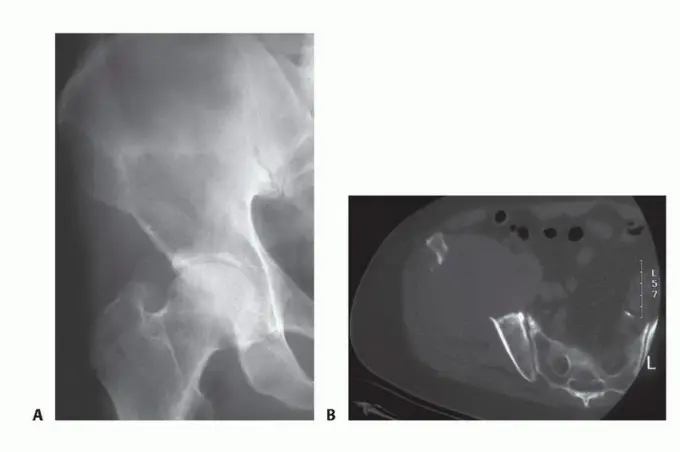

الشكل 1: أ. صورة أشعة سينية تظهر ورمًا نقيليًا في الحُق الأيمن لدى رجل يبلغ من العمر 72 عامًا ولديه تاريخ معروف بسرطان الغدة الدرقية. ب. يظهر التصوير المقطعي المحوسب (CT) تدميرًا واسعًا للعظام وامتدادًا للأنسجة الرخوة. محاولة الاستئصال بناءً على النتائج الشعاعية وحدها قد تؤدي إلى استئصال جزئي للآفة ونزيف محتمل بسبب الأوعية الدموية الكثيفة لهذا الورم. بالنظر إلى هذه النتائج الشعاعية، خضع هذا المريض لانسداد وعائي قبل الجراحة مما قلل من فقدان الدم أثناء الجراحة وسمح باستئصال ناجح.